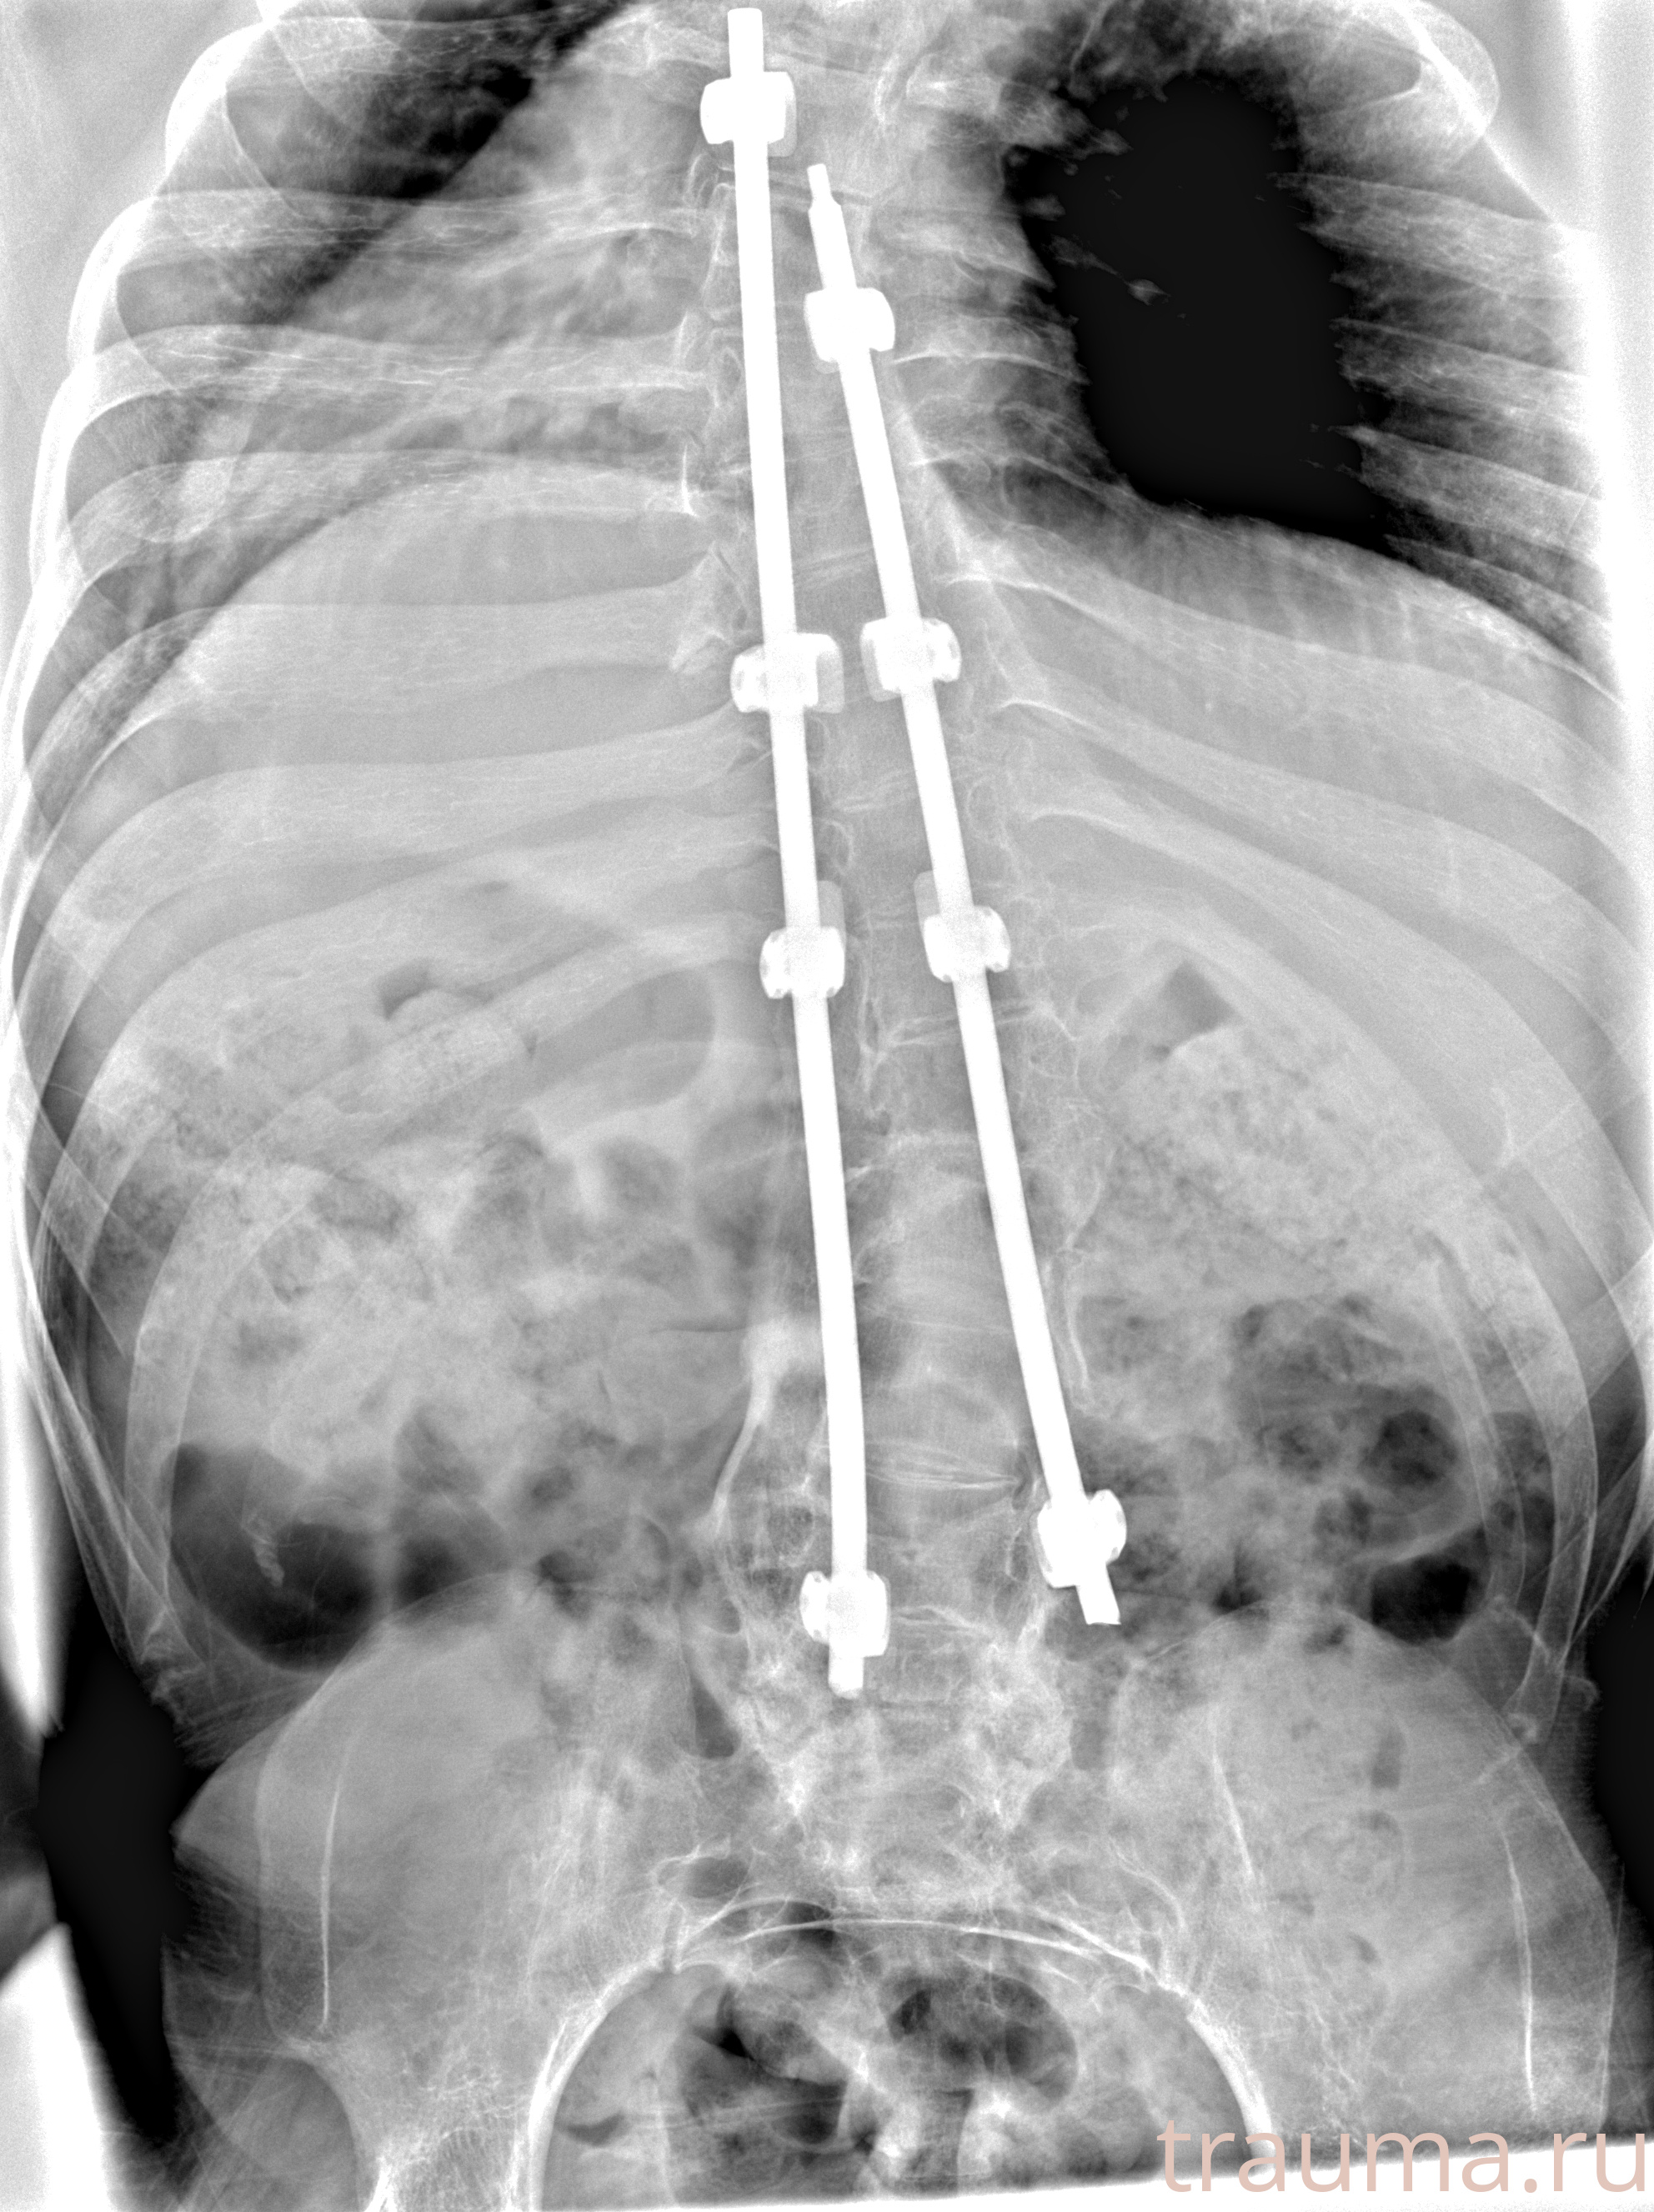

Рентгенограммы

Рентген на дому: по вашему адресу приезжает врач-рентгенолог, травматолог-ортопед с мобильным рентгеновским аппаратом, проводит диагностику травмы или заболевания, делает необходимые рентгенограммы, дает рекомендации по дальнейшему лечению. Получить качественные снимки в домашних условиях возможно благодаря уникальной методике, разработанной МосРентген Центром для института  Склифосовского